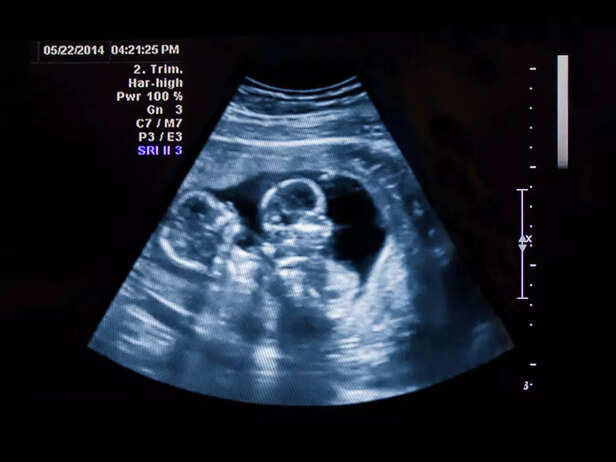

b. Ultrasound Evaluation

twin ultrasound

Early diagnosis is essential. Regular ultrasounds can help detect TTTS by measuring amniotic fluid levels and assessing blood flow within the placenta.

ultrasound

Doctors perform amnioreduction to remove excess amniotic fluid from the sac of the recipient twin. This helps reduce pressure on both babies.